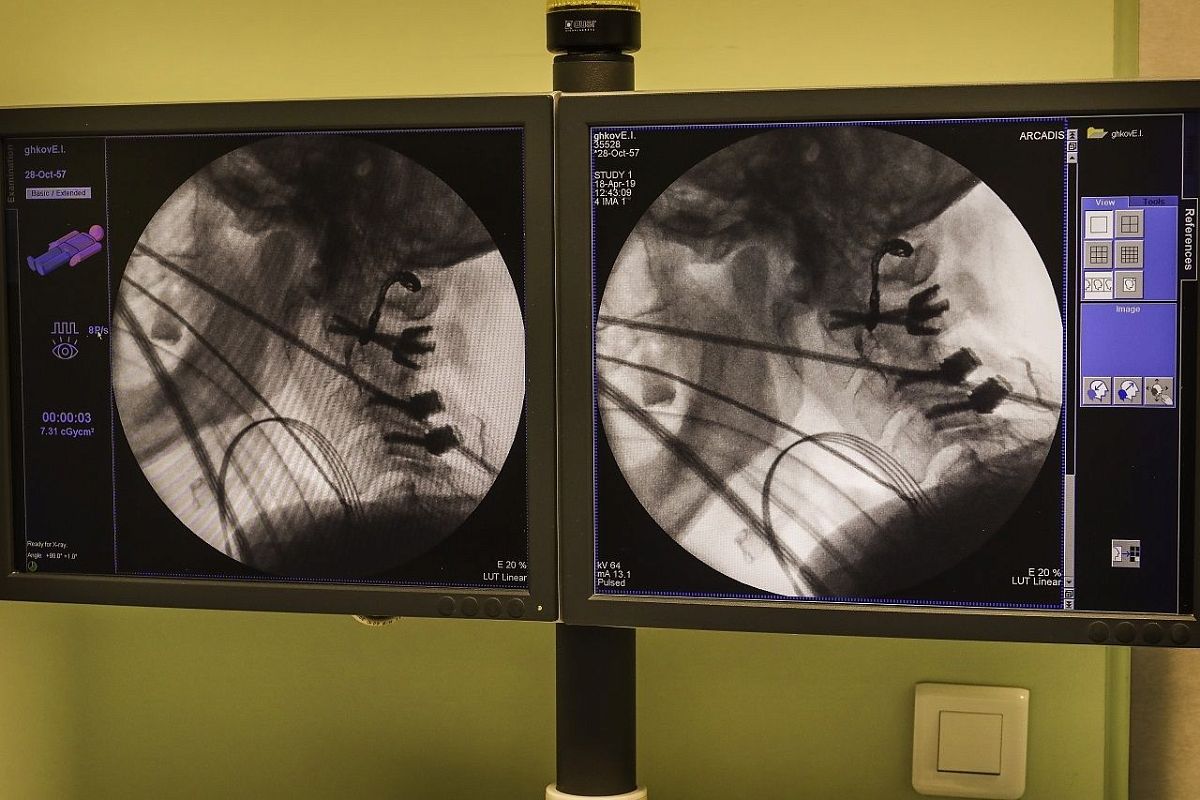

Уникальное вмешательство заняло 16 часов, пройдя четыре сложнейших этапа. Вначале рентгенхирурги остановили кровоснабжение опухоли, частично обезопасив работу с ней. Затем нейрохирург через задний доступ освободил часть опухоли от тканей, сосудов и спинного мозга и зафиксировал позвоночник. Далее челюстно-лицевой хирург распилил нижнюю челюсть пациента, тем самым открыв доступ к пораженному отделу позвоночника. После этого нейрохирурги завершили удалили опухоль цельным блоком через рот.